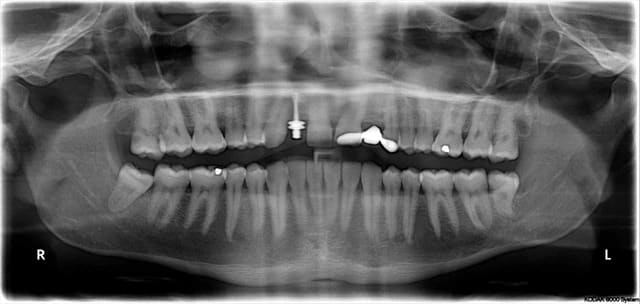

trop tard pour le guide je viens de poser l'implant

mais ton idée est très bonne Patrick, on va réussir à faire un guide fiable et pas cher pour poser ce genre de cas

bien sur à main levé c'est faisable!

utilisation de la clé de clio pour le centrage M-D

pano 1 oups!

pano 2 leger déplacement en mésial de la partie apicale de l'implant

c'est un 3.3x12